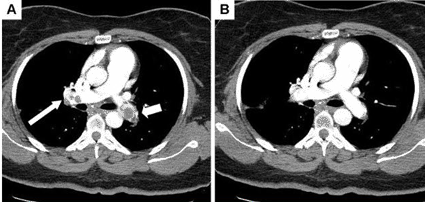

Multidetector CT Helps Identify Bullet Trajectories